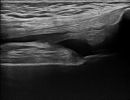

Μαλακά Μόρια Γόνατος

- Λιπώματα

- Γάγγλια

- Κύστεις Baker